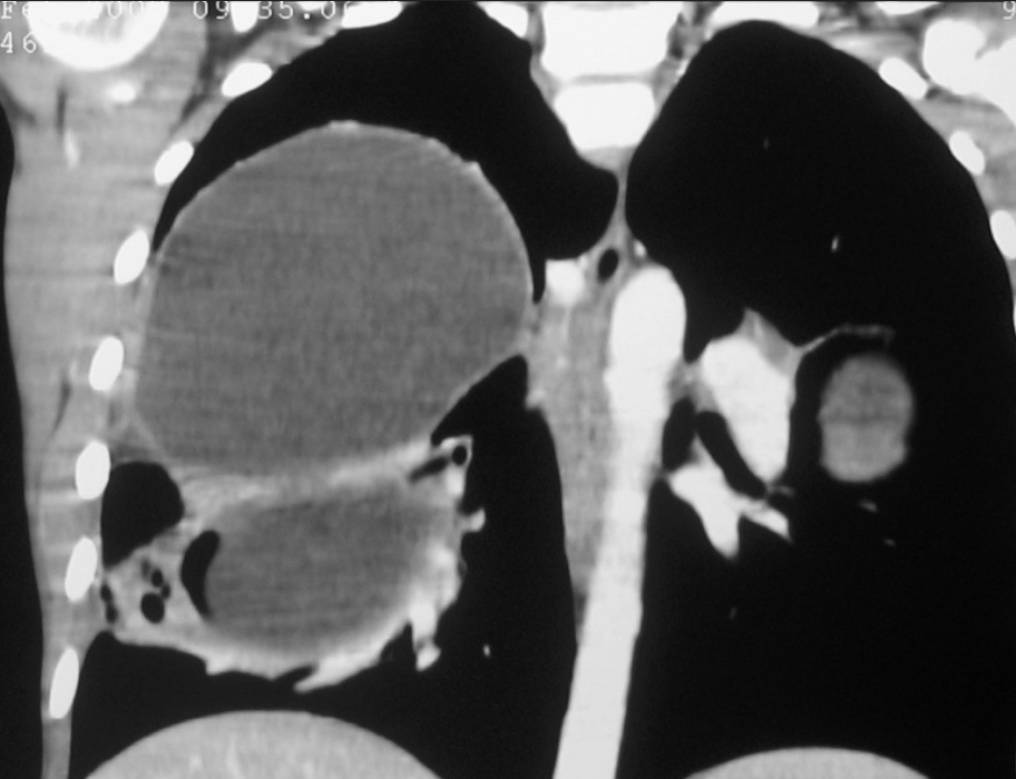

Chest X-ray revealed two nodular opacities (fluid density lesions) in right lung and one in left lung.

Thorax CT revealed two cysts in right lower and medium lobe of lung and one cyst in lingual lobe of left lung. The diagnosis of hydatid cysts was confirmed at surgery.